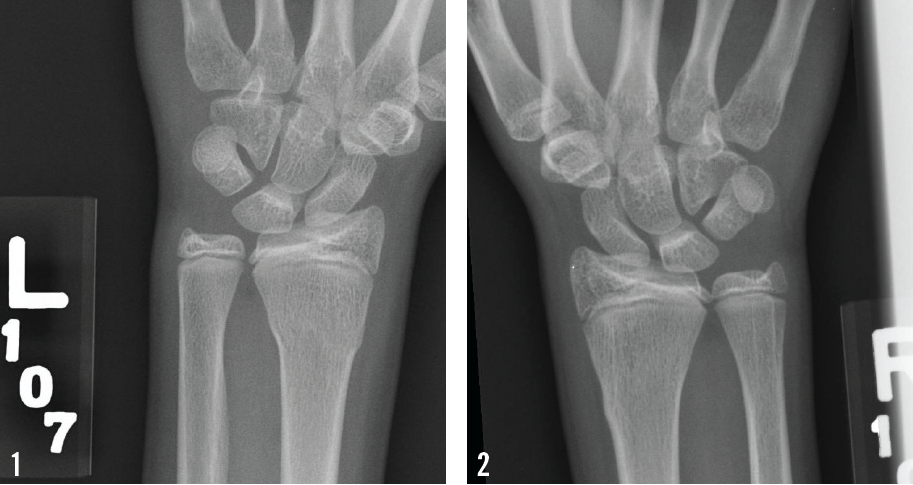

Suzanne M. Condron, MD

A 14-year-old girl presented to her pediatrician with a 1-day history of severe bilateral wrist pain. The patient, a runner and former gymnast, reported that on the day before, she had been weightlifting in...